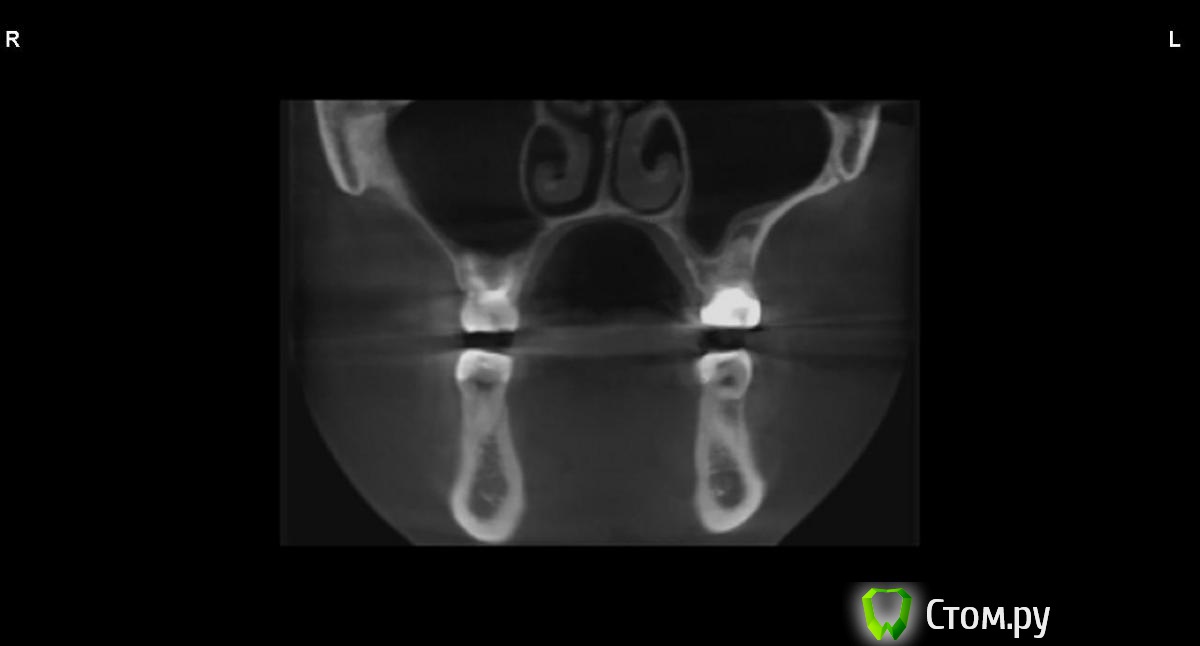

jm3300 Опубликовано 9 сентября, 2014 Автор Поделиться Опубликовано 9 сентября, 2014 вот, набросал Ссылка на комментарий

АнтонТЛТ Опубликовано 9 сентября, 2014 Поделиться Опубликовано 9 сентября, 2014 (изменено) это нижняя носовая раковина, возможно Изменено 9 сентября, 2014 пользователем АнтонТЛТ Ссылка на комментарий

АнтонТЛТ Опубликовано 9 сентября, 2014 Поделиться Опубликовано 9 сентября, 2014 я понял что это)))это артефакт от зуба, обратите внимание на правую сторону, там в пазухе тоже зуб есть, после эндодонтии)) Ссылка на комментарий